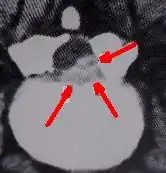

CT scan showing post operative scarring and arachnoiditis.

In a groundbreaking Canadian study, Waddell et al. reported on the value of repeat surgery and the return to work in worker's compensation cases. They concluded that workers who undergo spinal surgery take longer to return to their jobs. Once two spinal surgeries are performed, few if any ever return to gainful employment of any kind. After two spinal surgeries, most people in the worker's comp system will not be made better by more surgery. Most will be worse after a third surgery.[189]